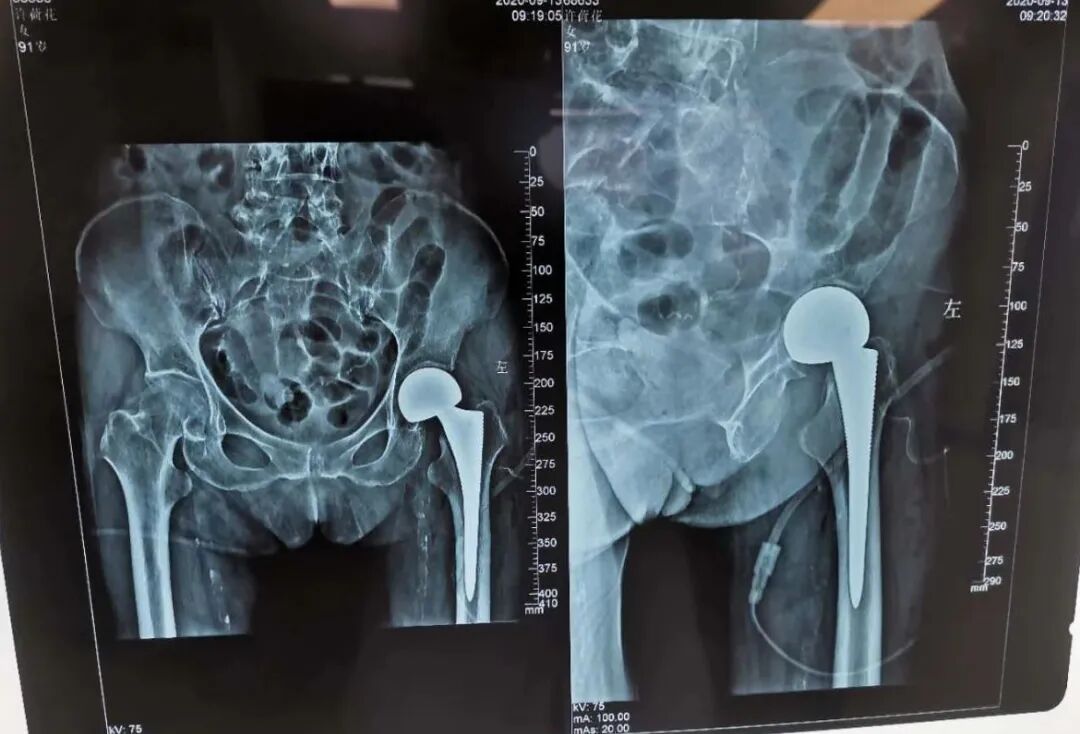

9月12日,术前经过充分的准备,手术采用腰硬联合麻醉方式,由麻醉科主任韩晓强亲自上阵,手术由朱宽宏院长和周亮主任主刀,经过1小时手术,刘阿姨手术非常成功,麻醉无恙、术中出血约100ml,随后,被送入重症监护室进行观察。

术后,在专业医护团队的细心护理下,第二天,刘阿姨便可以下床行走、下蹲、盘腿以及自己穿袜子,当刘阿姨家人看见这一幕时,这把他们都高兴坏了,刘阿姨家人道:衢州骨伤科医院朱院长和周主任你们太神了,不是亲身体验的话,别人说了我都不会相信呢,太感谢衢州骨伤科医院、感谢骨科全体医护人员、更感谢朱院长和周主任。我妈妈这个手术创伤很小,也不怎么疼,真是想不到现在医院的医疗技术发展的这么好”